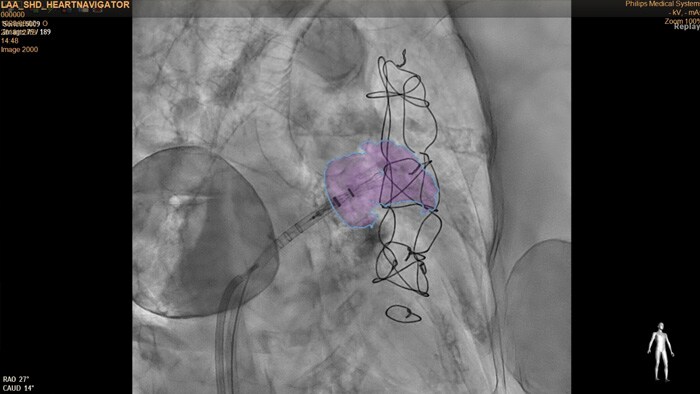

O HeartNavigator é uma solução de planejamento e orientação de camadas sobrepostas ao vivo para tomografia computadorizada usando segmentação automática da anatomia no modelo de coração para aumentar a facilidade de uso, velocidade e reprodutibilidade. Na oclusão do AAE, o HeartNavigator permite: